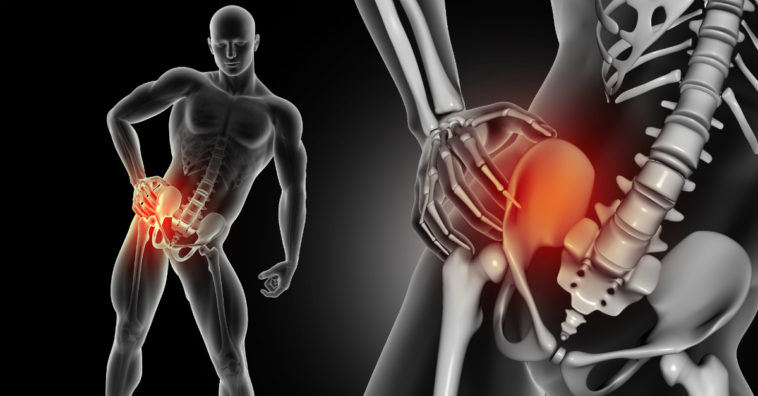

El dolor de cadera es un pesar que sufren diversas personas en algún punto de su vida. Éste, en la mayoría de los casos, no debe ser un síntoma preocupante. Conoce, a seguir, cuáles son las causas de este malestar y unos remedios caseros para tratarlo.

Causas del dolor de cadera

Si el dolor en la cadera persiste durante más de 2 semanas, es muy aconsejable visitar a un traumatólogo porque podría estar indicando que se está padeciendo una dolencia grave de huesos o articulaciones.